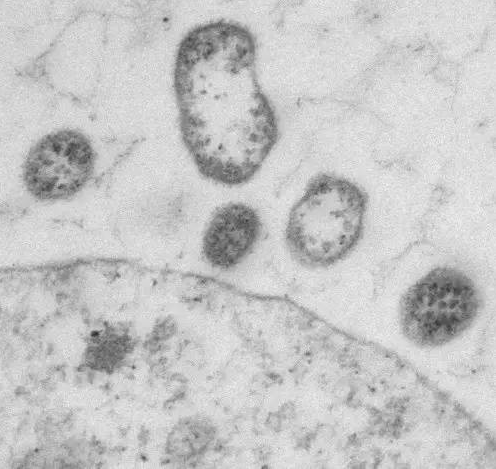

双靶点成功治疗多发性骨髓瘤

记者6月21日获悉���,南京传奇生物科技有限公司与西安交通大学第二附属医院合作展开的多靶点CAR-T疗法临床试验表现出惊人的客观缓解率,在近日举行的美国临床癌症学会年会上��,该疗法引起与会专家的高度评价和瞩目�。“患病后��,人体免疫细胞无法识别肿瘤细胞��,导致肿瘤快速复制转移病情扩散”���,南京传奇生物科技有限公司首席科学家兼创始人范晓虎说����,这种CAR-T疗法的特点是双靶点治疗,“目前大多数CAR-T疗法是一个靶点����,就像用一只手去抓球极易脱手,而双靶点相当于两只手去抓球����,成功率大大增加”。多发性骨髓瘤是三大血液系统恶性肿